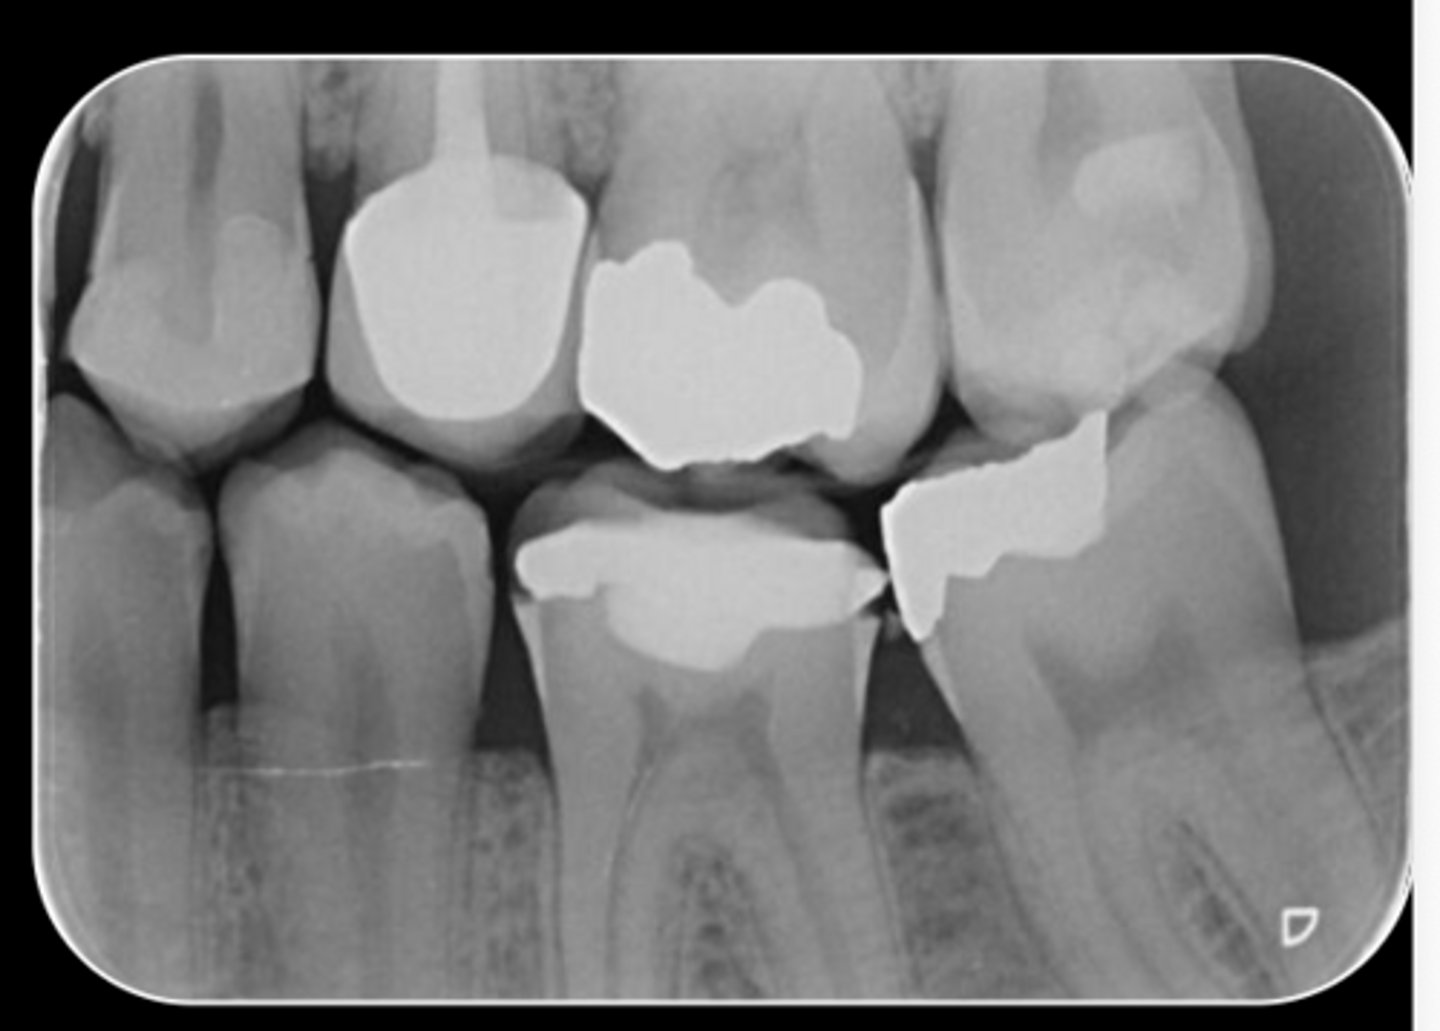

What are the radiographic findings on #19?

- Crown

- Post D Canal

- PARL Mesial and Distal Root

- PARL in Mesial and Distal Root

- Discontinuation of LD

What are the radiographic findings on #4?

- DO Composite

- RCT

- No PARL

- LD intact

- PDL normal